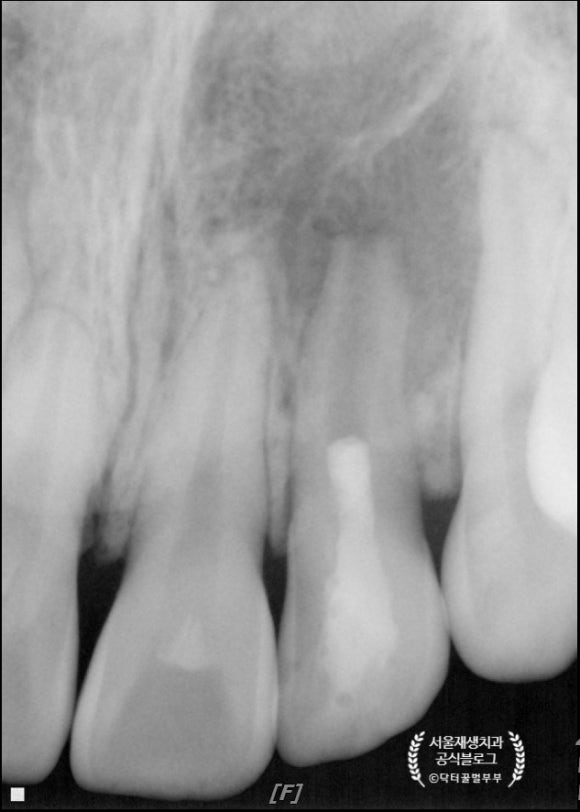

앗, 저런저런......

길다란 바늘이 위치한 치아가 보이시나요?

치아 뿌리를 중심으로 까맣게 뼈가 녹아내린 소견입니다.

성장중이던 치아의 생활력이 상실되어

(=신경이 죽어서)

죽은 조직으로 인해 염증이 유발되고,

치근의 성장 또한 멈춘 전형적인 문제 사례입니다.

원인은 외상이라고 합니다.

예전에 넘어진 적이 있었지만, 당시엔 증상이 없어서 그냥 지나갔다구요.....ㅠ